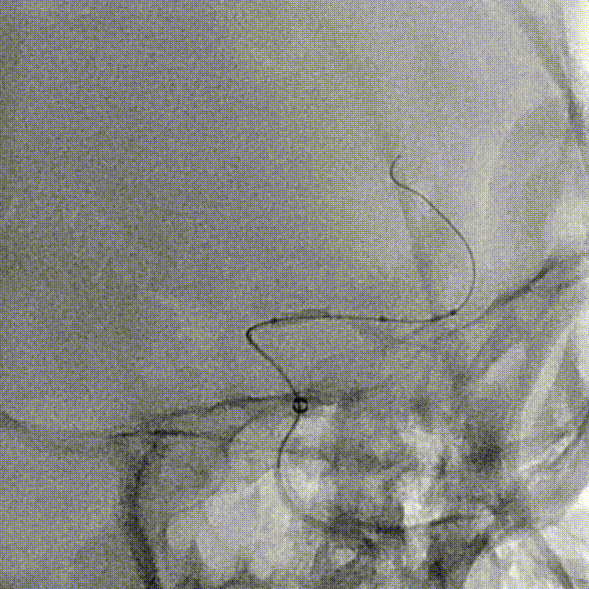

撤出微导丝后,经Fastunnel®输送型球囊扩张导管送入3.0mm*16mm NeuroStellar®颅内支架,支架到位后调整释放张力后定位支架。

术中缓慢释放NeuroStellar®颅内支架头端后系统稳定,随后释放至支架尾端,造影提示支架打开满意,贴壁满意。